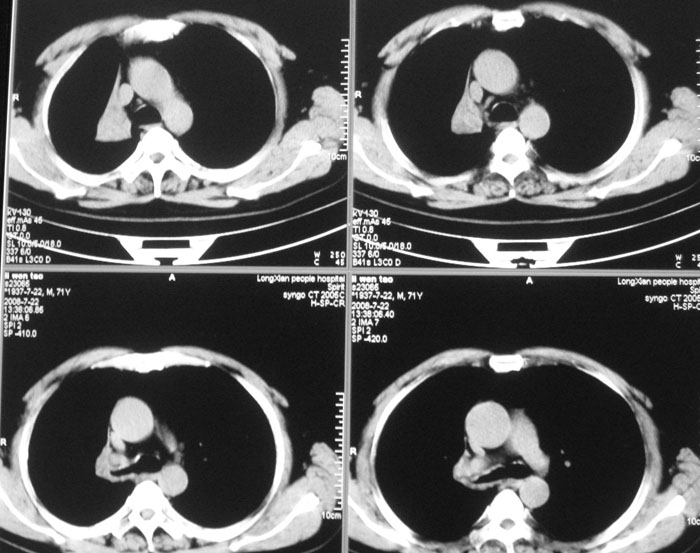

以下是引用wwwwtyy在2008-7-27 17:46:00的发言:[br]中心型肺癌不除外

以下是引用子十在2008-7-27 17:49:00的发言:[br]考虑中心性肺癌

以下是引用晓杰在2008-7-27 19:20:00的发言:[br]支持楼主意见;中心型肺癌不除外。

以下是引用zhangjixiang在2008-8-6 20:02:00的发言:[br]右主支气管明显变窄伴右上叶尖段不张,结合年龄,考虑右侧中央型肺癌可能性大,纤支镜检可确诊.